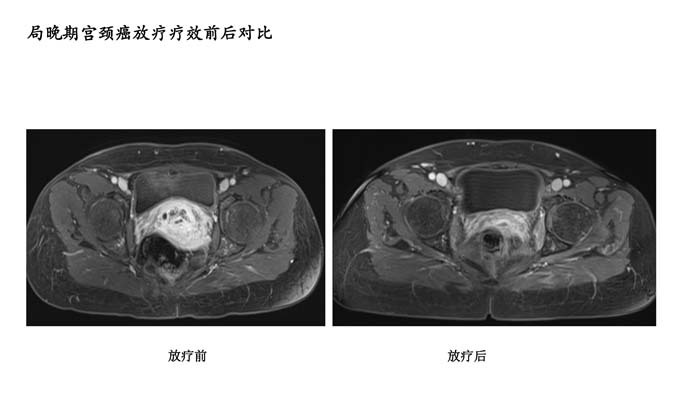

上一篇: 局部晚期鼻咽癌放疗疗效前后对比4

下一篇: 局晚期宫颈癌放疗疗效前后对比2